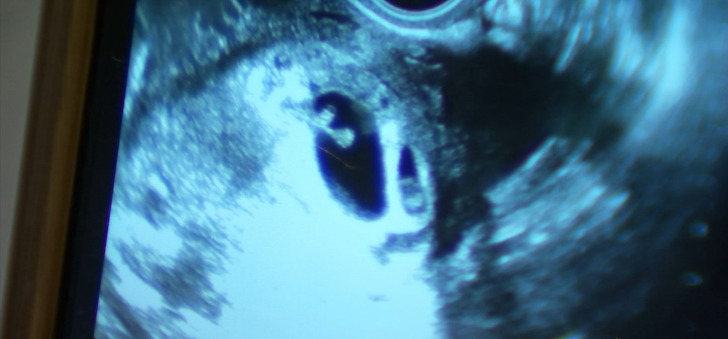

Кара Винхолд останала бремена во март 2021 година, но тоа го чувала во тајност. Таа претходно се соочила со 3 спонтани абортуси и не сакала да се возбудува додека не се увери дека се е во ред со бебето. Конечно, неколку месеци подоцна, ултразвукот открил дека има бебе и дека е здраво. Но, лекарите откриле нешто смешно на сликите.

Парот бил збунет: „Што сакате да кажете, чукање на срцето на другото бебе?“ Така докторот потврдил дека имаат 2 бебиња, ги видел и двете на ултразвук. Идните родители биле шокирани; тие навистина имаа близнаци!